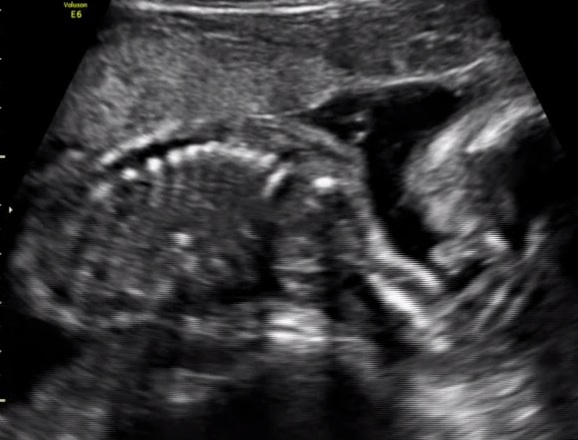

All I can make out there is spine, so bumping for you x

Sent from my iPhone using Tapatalk

Dont know what im looking at :(

Did they give you any other photos? No visible gender clues here.